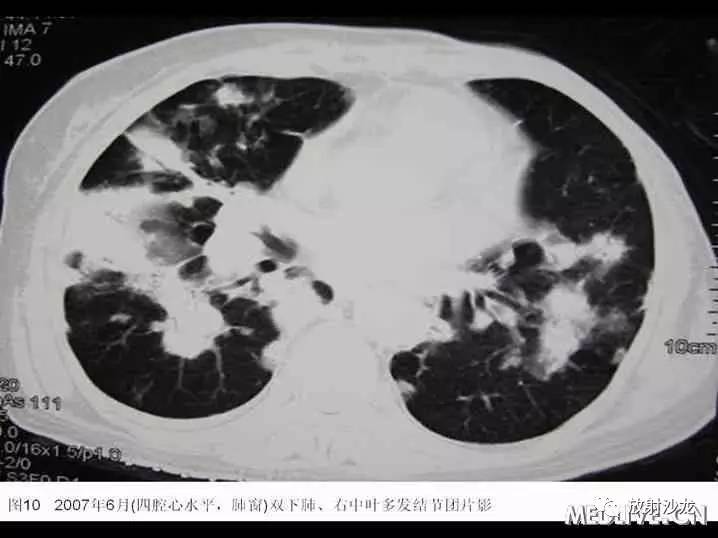

患者于2006年4月初无诱因出现间断咳嗽,少量黄痰,无咯血、胸闷、胸痛。2006年4月中下旬出现发热,最高体温38℃,当地血常规:WBC:6.7G/L,GR:78%,胸片示“右下肺纹理增粗,局部可见斑片索条影,右侧肋膈角钝”;考虑“肺部感染”,予拜复乐(莫西沙星)、罗氏芬(头孢曲松)治疗3天后体温降至正常,但仍有间断咳嗽、咯痰,遂于2006年5月中旬就诊某一上级医院,胸部CT“右下肺及胸膜下可见多发结节、斑片影,局部可见支气管扩张”(见图1-4),行胸腔镜肺活检,病理经多家医院综合会诊后考虑“淋巴组织增生性病变,但是诊断淋巴瘤证据不够”,未予特殊治疗。

入院后患者最高体温在38℃左右,给予“拜复乐及大扶康”治疗后无显效,复查胸部CT提示肺内病变较2007年3月有加重(见图9-12),遂再次行CT引导下经皮肺穿。穿刺后患者最高体温维持在39℃左右,考虑感染不能完全除外,于2007年6月19日起加用稳可信0.5g Q8h及复达欣1.0g Q8h,6月21日加用口服大扶康200mg Qd,发热未见改善。结合两次肺穿及外院VATS的标本,病理科诊断“肺Castleman病(多中心型)(见图13)” 免疫组化:CD3(+)、CD20(+),AE1/AE3(+),CD21(+)”。6月21日转入血液科化疗,并于6月22日予CHOP方案化疗(CTX 600mg d1, 400mg d4, 西艾克4mg d1, 艾达生80mg d4, 强的松80mg d1-5)。化疗后未再发热,咳嗽、咳痰症状缓解,6月27日复查CXR示右下肺团块影较1月前吸收予以一疗程CHOP化疗后,患者体温正常,复查胸片提示右下肺阴影较前有明显吸收。后又间断予以CHOP方案化疗3程,2008年2月初,因受凉后发热,出现渐加重的气短,家属及患者放弃进一步诊疗,于2008年2月下旬去世。